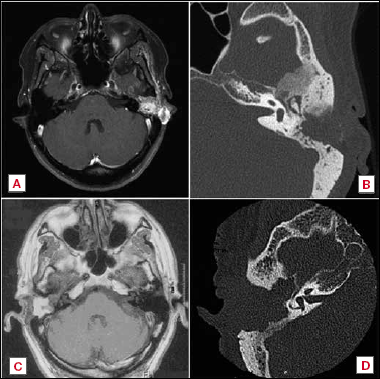

Histopathology

In all three patients, the specimens of the tumour in the temporal bone, the lymph nodes and liver metastasis showed the same basic histology. In patient 1, microscopic examination revealed a tumour composed of atypical epithelial cells with a cribriform growth pattern (Fig. 2). The cells showed pleiomorphism, sporadic nucleoli and sparse eosinophilic cytoplasm. The tumour invaded the petrosal bone including the cochlea. Immunohistochemistry showed positive staining for synaptophysin and chromogranin A. Mitotic figures were rare and the Ki-67 labelling index was < 2%.

Figure 1. CT and MR imaging of the middle ear neuroendocrine tumours of patient 1 (A and B) and patient 2 (C and D). A) Axial T1-weighed MRI scan, demonstrating the primary tumour as a mass in the left mastoid with extension to the temporal fossa and preauricular region; B) Axial temporal bone CT, showing soft tissue in the left middle ear cavity with suspicion of erosion of the malleus and anterior temporal bone; C) Axial T1-weighed MRI scan, demonstrating the recurrent right middle ear mass at the level of the cochlea; D) Axial temporal bone CT, showing soft tissue completely filling in the right middle ear cavity.

Figure 2. Histopathological findings (haematoxylin and eosin) of the (A) primary middle ear tumour and (B) liver metastasis of patient 1. In both tumours features of middle ear neuroendocrine tumours can be observed: atypical epithelial cells with a cribriform growth pattern associated with fibrous stroma in the background. The tumour cells showed mild pleiomorphism, sporadic nucleoli and sparse eosinophilic cytoplasm. Immunohistochemical stains for synaptophysin show strong positivity within tumour cells. Mitoses were not seen and Ki-67 (MIB-1) staining showed < 2% positive tumour cells in both the primary tumour (C) and liver metastasis (D).